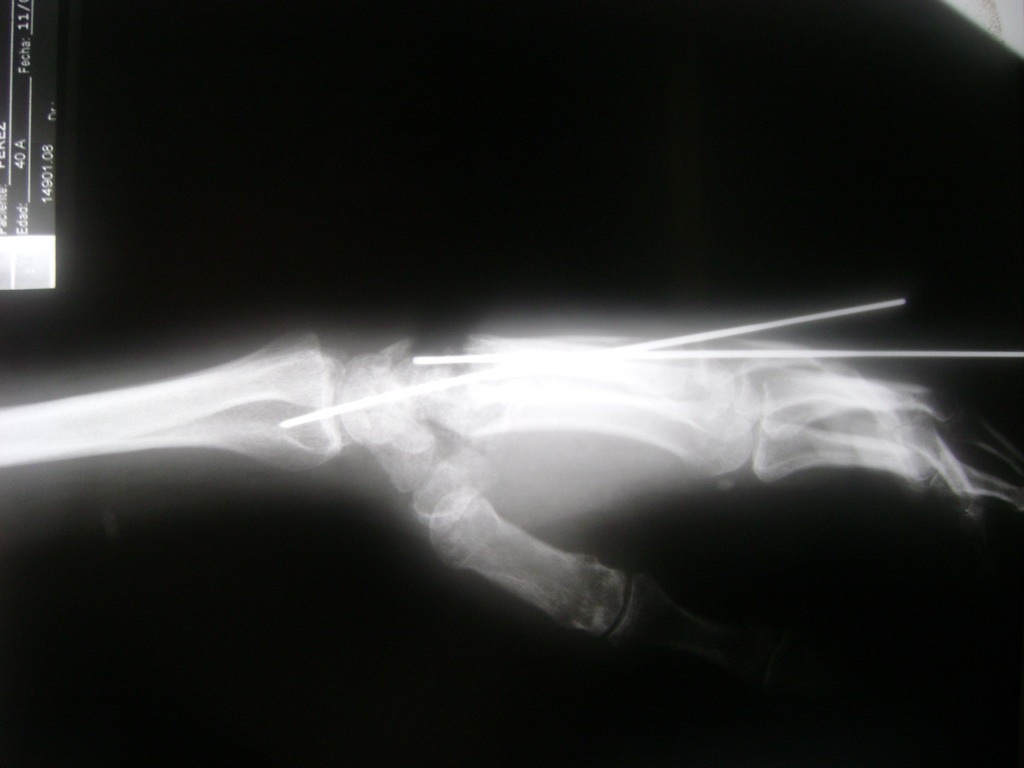

Clavícula